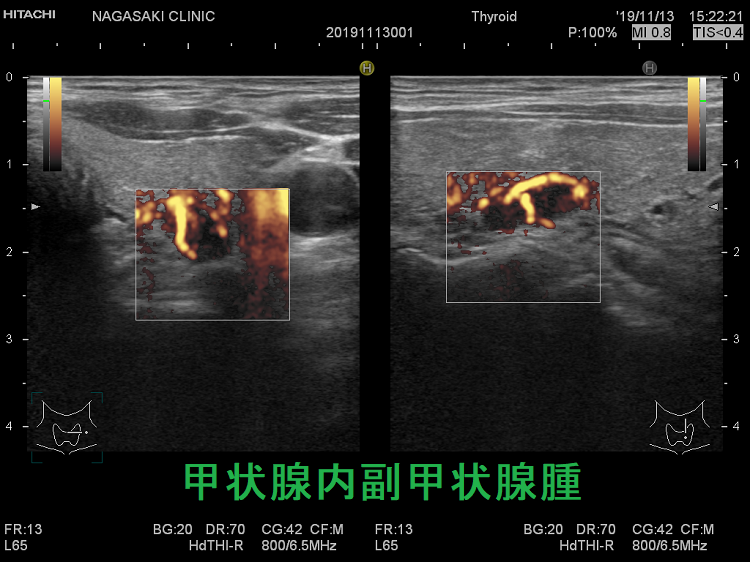

甲状腺内副甲状腺腫は、原発性副甲状腺機能亢進症の1.4 ~ 2.1%を占めます[Surgery. 2009 Dec;146(6):1144-55.]。

甲状腺内副甲状腺腫は、超音波(エコー)検査で甲状腺腫瘍と形態的に鑑別できない場合があります(実際は下の写真のように診断できていますが・・)。特徴的な超音波(エコー)所見は、腹側の高エコーで感度86%、特異度100%です[Surgery. 2012 Dec;152(6):1193-200.]。さらに、99m-Tc MIBIシンチグラフィーで取り込み(集積)があれば甲状腺内副甲状腺腫と診断できます。

99m-Tc MIBIを取り込まない甲状腺内副甲状腺腫もあるため、穿刺細胞診を行い、針先洗浄液でインタクトPTHを測定(FNA-PTH)。甲状腺内副甲状腺腫は、甲状腺が周囲にあるため、針に沿った副甲状腺細胞のばらまき(播種)・出血の危険が少なくなります。

腺腫様甲状腺腫に合併する甲状腺内副甲状腺腫

腺腫様甲状腺腫に合併する甲状腺内副甲状腺腫は、腺腫様結節と鑑別が難しいだけでなく、多腺性(5-6腺)のケースがあります。

(第55回 日本甲状腺学会 P2-09-10 バセドウ病と甲状腺内副甲状腺腫を合併した1 例)[頭頸部外科 24(2):207-216, 2014]